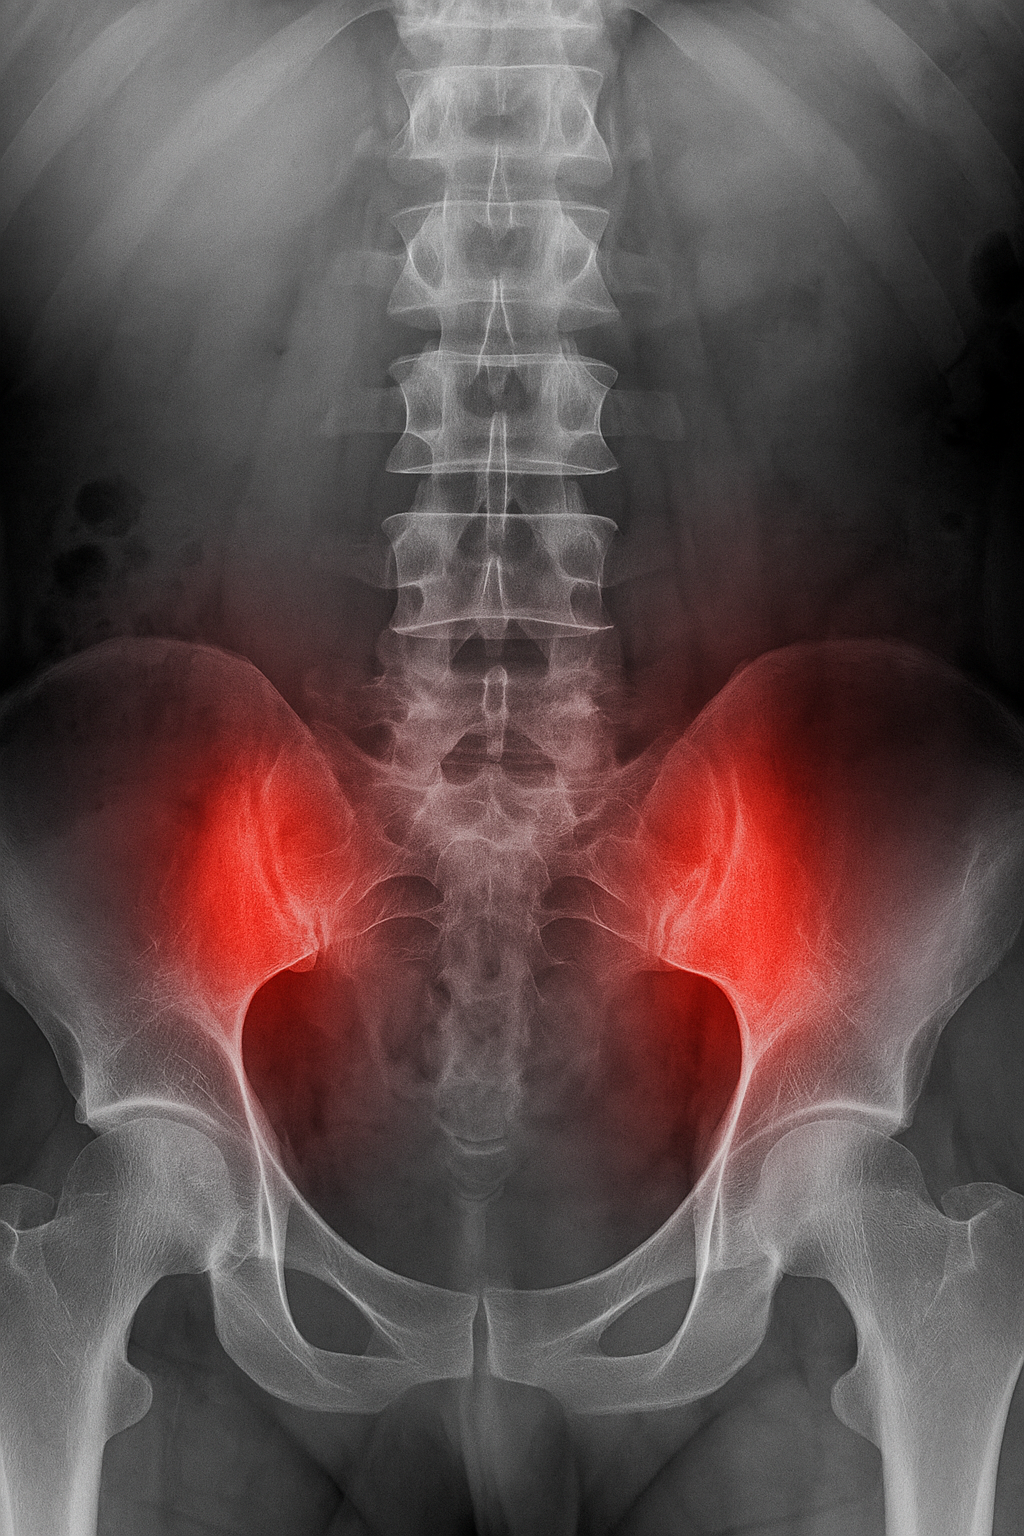

Black and white X-ray image of the lower spine and pelvis with red highlighting over the sacroiliac joints to indicate inflammation.

Inflammatory back pain comes from inflammation in the spine or sacroiliac joints (SI joints). This can be due to an underlying autoimmune condition, often in the spondyloarthritis (SpA) family.